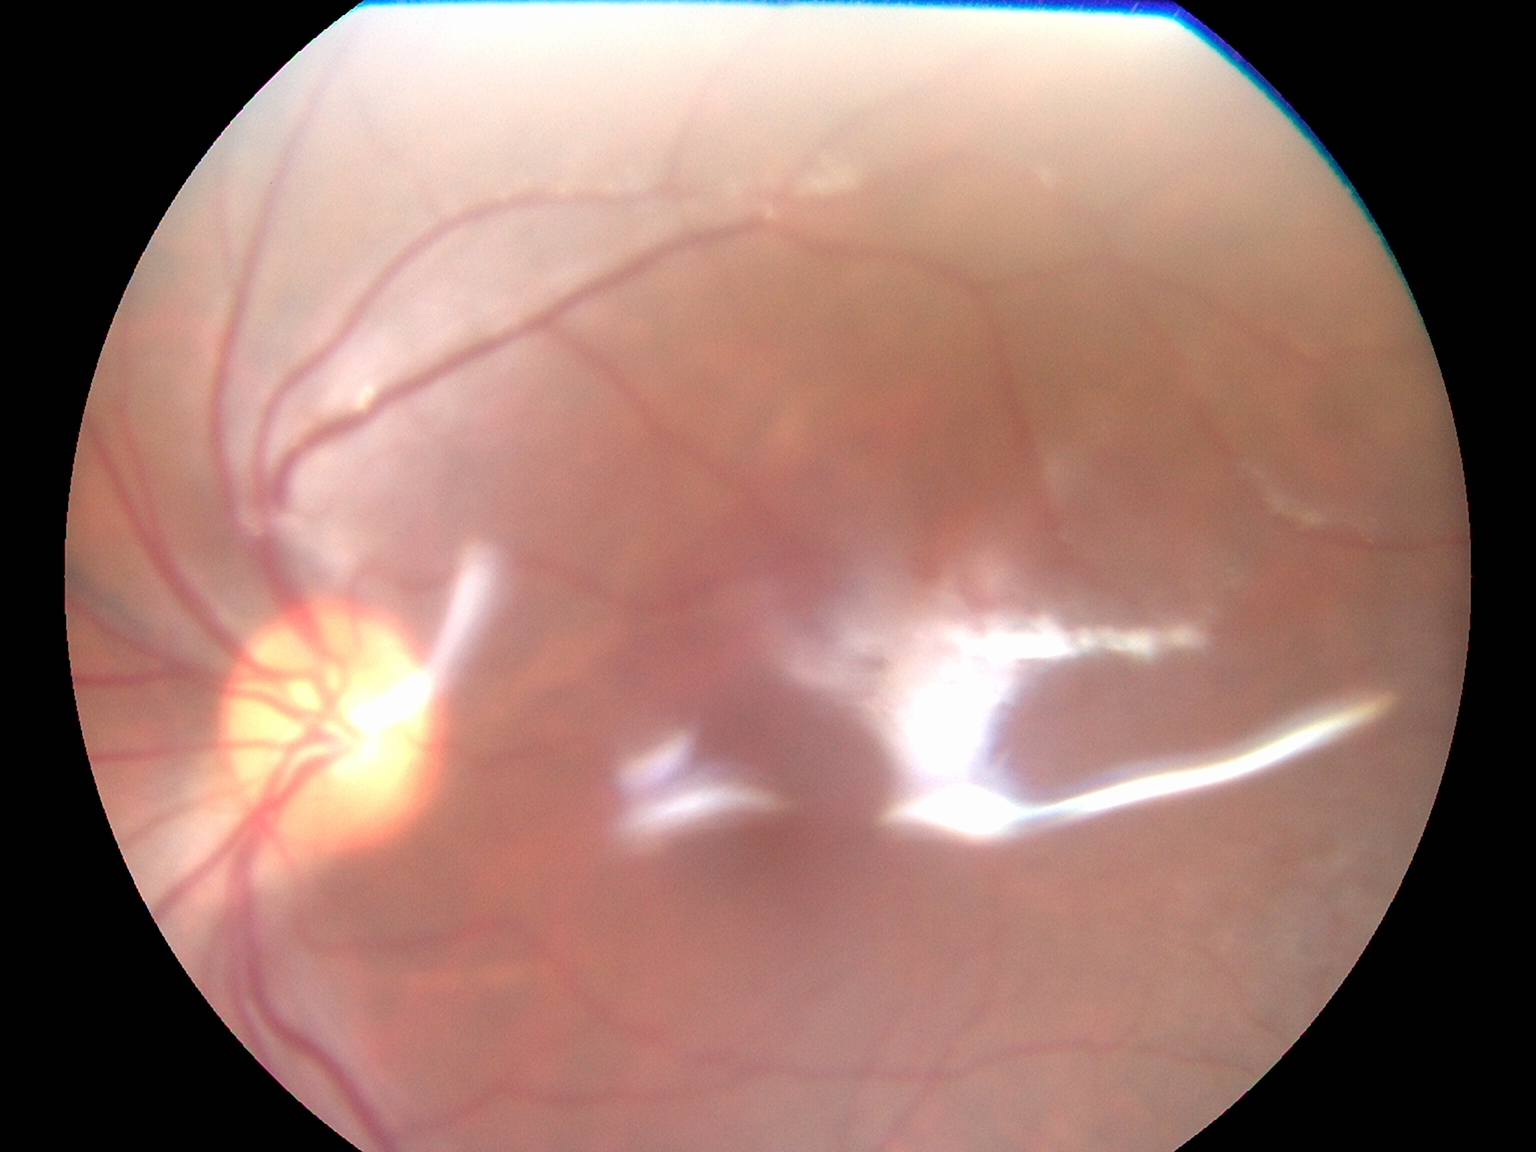

Top Retina Specialist

Advanced Retina Treatment